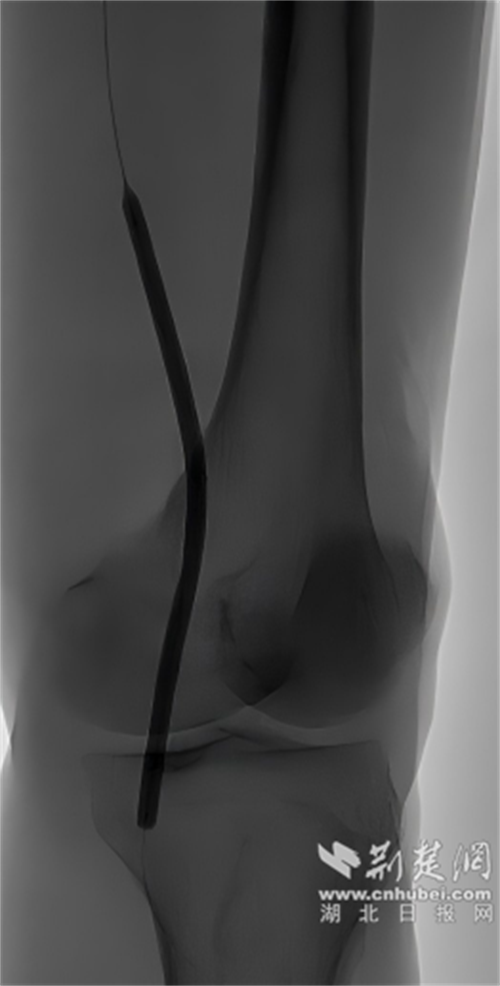

来国药东风总医院就诊时,血管造影显示了一个严峻的现实——郝伯伯左侧腘动脉狭窄达90%,双侧胫前动脉闭塞。这正是导致他剧痛和行走困难的根源。

下肢动脉介入治疗前。通讯员 供图